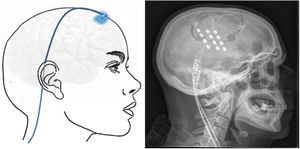

Technique. With the patient in the prone decubitus position, a vertical incision is made from 1 cm above to 1 cm below the occipital protuberance, along the midline. Subsequently, vertical incisions are made 4 cm either side of the midline, and the muscle fascia is exposed; electrodes are inserted extracranially at the level of the occipital bone and fixed using horizontal plates (Fig. 4). The electrodes are placed above the GON and lesser occipital nerve, stimulating both. Leads are placed by subcutaneous tunnelling along the midline to a middle thoracic level. From there, the lead is run to the upper buttock, where the generator is placed subcutaneously. The length of the lead is adapted to the patient’s anatomy, and its course includes a loop to prevent disconnection of the lead during forced cervical postures (Fig. 5). The electrodes may also be placed percutaneously above the occipitalis muscle fascia. Various techniques and systems have been described, with different types, directions, and numbers of electrodes and different anatomical placements of the generator.

Transcortical neuromodulationTechnique. MRI is used to locate the area of facial pain, anterior to the Rolandic fissure at the level of the inferior frontal sulcus. With this information, neuronavigation-guided craniotomy is performed with the patient under local or general anaesthesia. The cortical area representing the hand is located using intraoperative evoked potentials. The electrodes (generally 4) were initially implanted subdurally, but epidural placement is now used to avoid complications (Fig. 6). After verifying the proper placement and functioning of the device, the electrodes are connected to a subclavicular generator with a lead placed via subcutaneous tunnelling.142–145